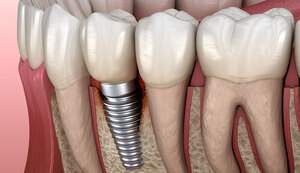

インプラントとは、虫歯や歯周病などの様々な原因により歯が失われてしまったところへ、人工の歯の根=人工歯根(インプラント)をつくり、その上に被せ物を装着する治療法のことです。

インプラントの特徴は、歯根まで再現し骨とインプラントが直接結合することにより、天然歯と同じような見た目・機能の両面において元の自然な状態へ近づくことができ、またしっかり噛むことができます。

インプラントの構造は、上部構造・アバットメント部(支台部)・歯根部の3つの構造から成り立っています。

上部構造は、いわゆる被せものを指しており、歯の部分です。

アバットメント(支台部)は、上部構造と歯根部をつなぐ役割を果たしています。

歯根部は、チタン製で、この部分と顎の骨が結合します。